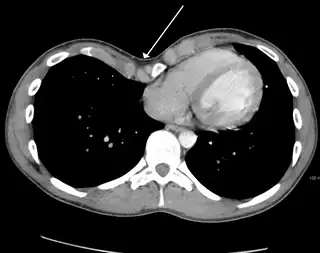

Pleural effusion

.jpg)

A pleural effusion is an accumulation of fluid inside the pleural space. If this collection of fluid gets large enough, it can also push structures in the chest away from it and cause a mediastinal shift. However, a pleural effusion can also pull the mediastinal structure towards itself. If this is the case, then there is an underlying condition causing the collapse of the lung on that side. An example is a tumor obstructing a bronchus and causing lung collapse and pleural effusion.[3]